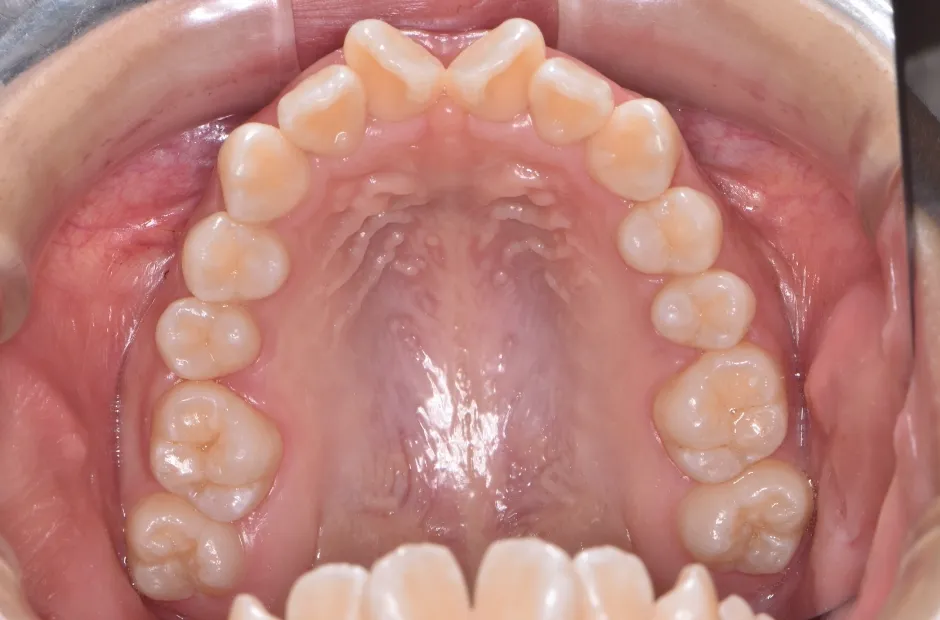

前歯部反対咬合

| 診断名・主訴 | 前歯部反対咬合 |

|---|---|

| 年齢・性別 | 14歳・男性 |

| 治療期間・回数 | 1年2か月 |

| 治療に用いた主な装置 | ブラケット矯正 |

| 抜歯部位 | なし |

| 治療費 | 60万円(税抜) |

| リスク・副作用 | 装置による違和感・疼痛・歯肉退縮・歯根吸収・虫歯のリスクなど |

治療前

治療後